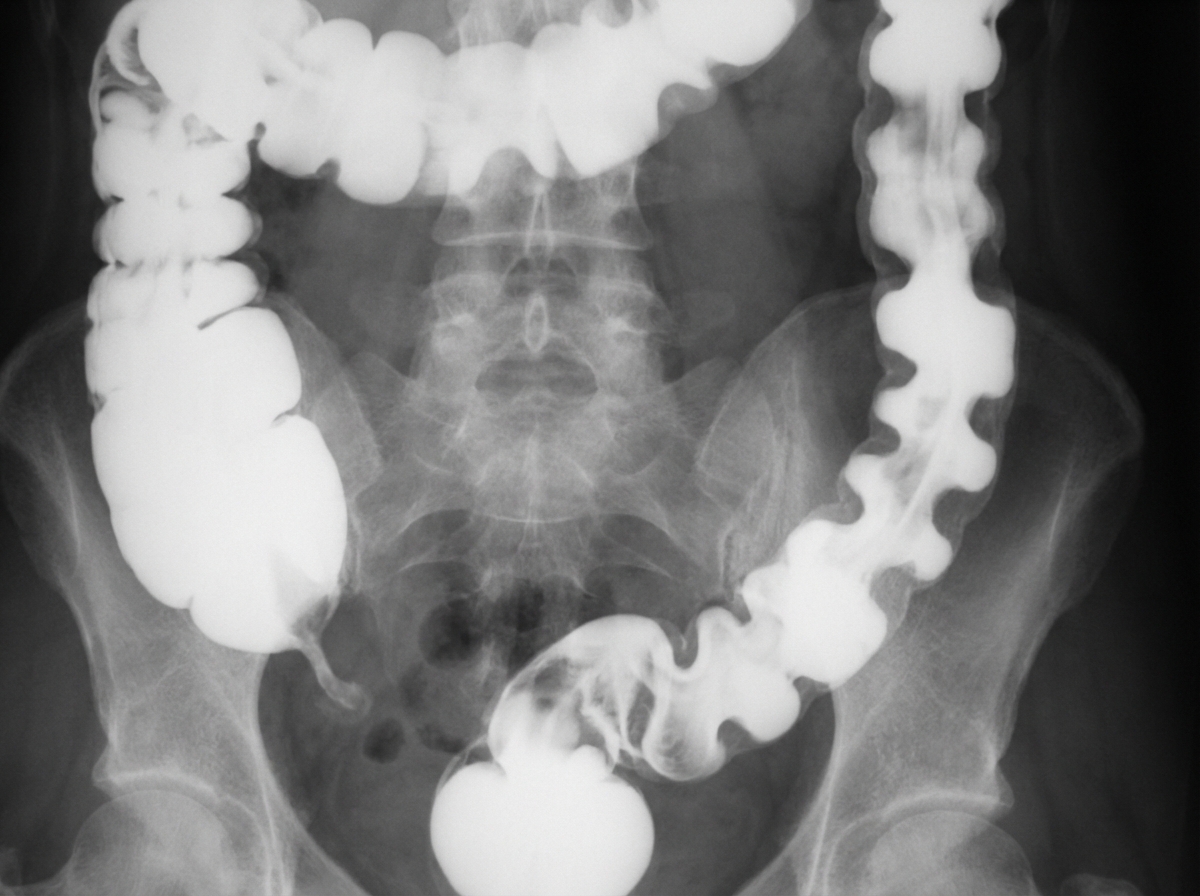

A 70-year-old man presents with severe crampy abdominal pain which is worse after eating. The patient also complains of frequent nausea, bloating, watery diarrhea, and weight loss. His other medical problems include coronary artery disease, hypertension, and hypercholesterolemia. He has a 30-pack-year smoking history. A barium enema is shown. Which of the following statements is true?

Explanation: ***Screening of the described condition can be done by duplex ultrasonography (pre and post-prandial).*** - The clinical picture describes **chronic mesenteric ischemia** with classic **postprandial abdominal pain**, weight loss, and vascular risk factors. - **Duplex ultrasonography** comparing pre and post-prandial flow velocities in mesenteric vessels is a valid **non-invasive screening tool** for mesenteric ischemia. *Barium enema is suggestive of diverticulosis.* - The barium enema likely shows **thumbprinting** pattern, which indicates mucosal edema from **ischemia**, not diverticulosis. - **Diverticulosis** would show characteristic **outpouchings** of the bowel wall, not the smooth indentations seen in ischemia. *Contrast-enhanced MRI is the investigation of choice.* - **CT angiography** or **conventional angiography** are the gold standard investigations for mesenteric ischemia, not MRI. - **MRI** has limited utility in evaluating **mesenteric vessels** and is not the preferred modality for this condition. *Treatment includes patient counseling, amitriptyline, NSAIDs, and steroids in severe conditions.* - This treatment regimen is appropriate for **irritable bowel syndrome (IBS)**, not chronic mesenteric ischemia. - Treatment for mesenteric ischemia involves **revascularization** (surgical bypass or angioplasty) and management of **atherosclerotic risk factors**.